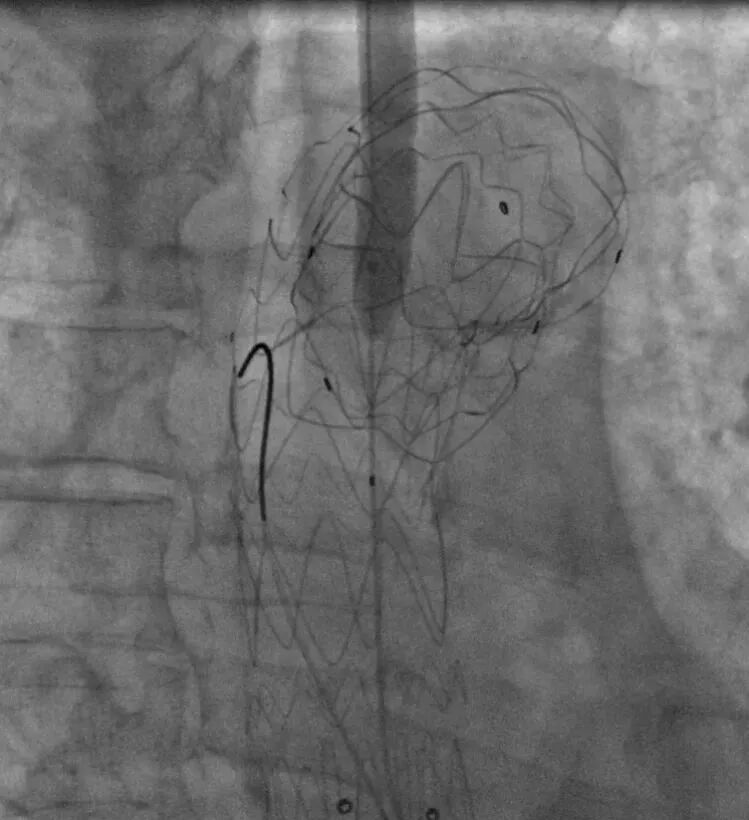

1. 患者仰卧位,常规消毒,铺无菌单,全麻成功后穿刺右侧股动脉,引入短鞘备用;切开左侧肱动脉,穿刺引入导丝,置入8.5F可调弯鞘,引导金标猪尾造影导管至升主动脉水平造影示主动脉弓部巨大瘤样扩张,与术前CT一致。

LAO造影

RAO造影